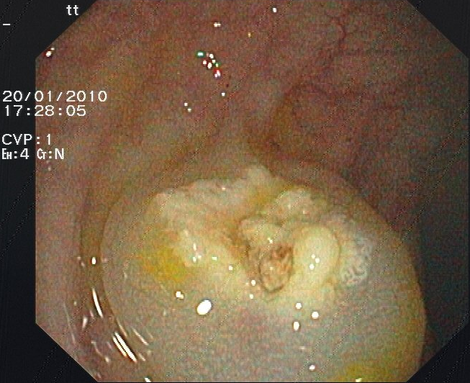

Chromoendoskopie

Manche Schleimhautveränderungen im Magen-Darm-Trakt sind bei der Endoskopie nur schwer zu erkennen bzw. abzugrenzen. Bei der Chromoendoskopie werden Farbstoffe auf die Schleimhaut aufgesprüht, dadurch werden Schleimhautveränderungen besser hervorgehoben. Proben können dann gezielt entnommen werden.

Eingesetzt werden absorptive Färbemittel, die von bestimmten Zellen aufgenommen werden, und Kontrastfärbemittel, die sich auf die Schleimhaut auflagern und das Schleimhautrelief verdeutlichen.

Zu den absorptiven Farbstoffen gehört z. B. Lugolsche Lösung, die im Ösophagus eingesetzt wird und der Früherkennung von Krebsvorstufen dient, die sich im Gegensatz zu normaler Schleimhaut nicht anfärben (Abbildung 2).

Als Kontrastfärbemittel wird im oberen und unteren Gastrointestinaltrakt zur besseren Erkennung und Abgrenzung von Polypen bzw. Krebsvorstufen Indigokarmin verwendet (Abbildung 1). Essigsäure wird in der Speiseröhre zur besseren Beurteilbarkeit eines Barrett-Ösophagus aufgebracht (diese Veränderung gilt ebenfalls als Krebsvorstufe).